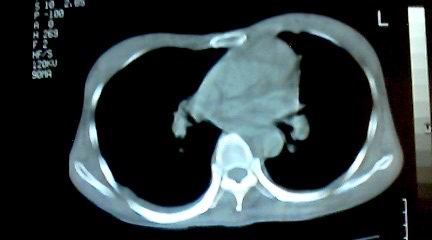

标题: CT25218:请教!胸部CT,胸8椎体骨质破坏,伴周围软组织肿。

患者,女41岁,肢体乏力。

两肺上叶继发性肺结核;胸椎结核并椎旁寒性脓肿形成。

胸椎结核并椎旁寒性脓肿形成。

恶性,椎体淋巴瘤或pnet并肺内转移。